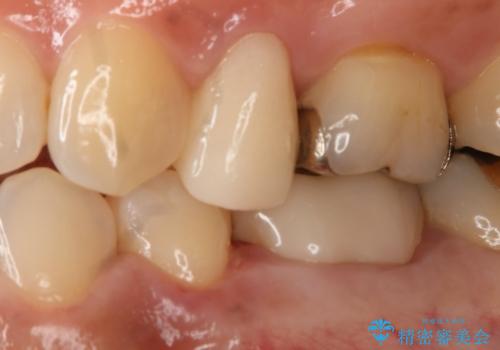

- 左下5番の銀歯をセラミックにやり変え希望の患者様です。

切削量を考慮し、セラミックインレーでの治療を選択しました。

銀歯直下のう蝕を除去しCRで裏層を行った上で、形成・印象を行っています。